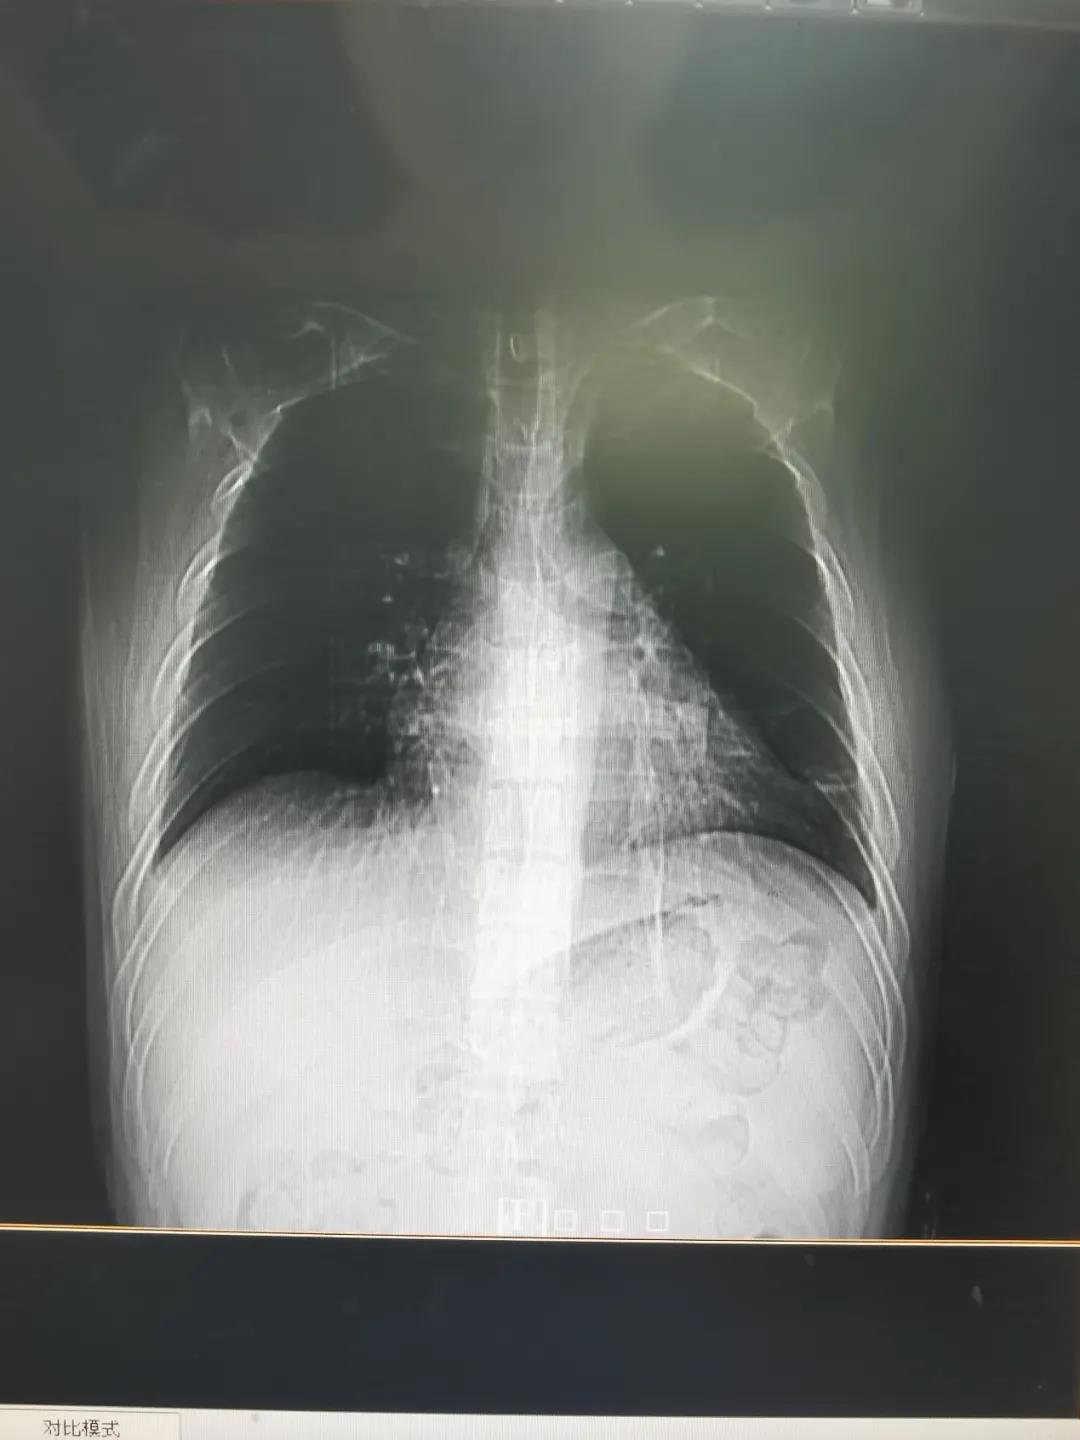

治疗后胸片:渗出灶全部吸收